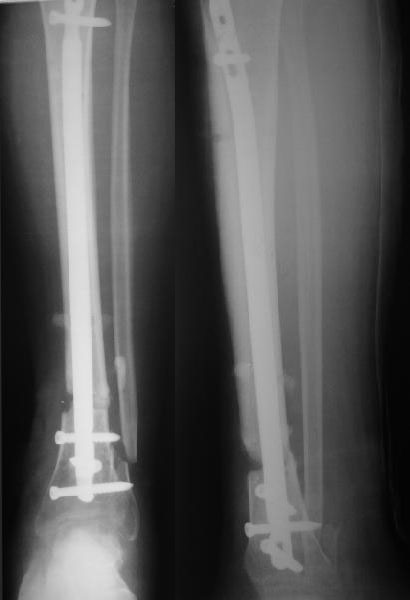

Здравствуйте коллега! Интересный случай! Буквально 3-4 месяца назад столкнулся с подобной ситуацией. Плюс у больного имелась нейропатия малоберцового нерва, стойкая эквинусная деформация стопы. Молодой человек лечился в другом лечебном учреждении. Первым этапом выполнено удаление стержня ChM, наложен аппарат внешней фиксации, в течении недели проводилось устранение имеющихся деформаций. Вторым этапом выполнен ЗИМО стержнем MetaDiaFix-T большего диаметра (картинки в приложении).